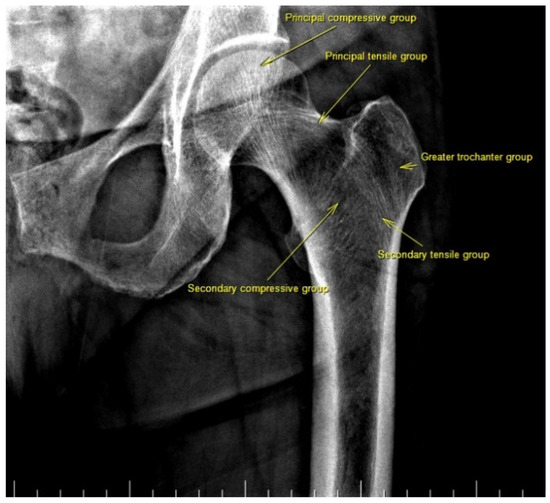

There are also osteoporosis measurements that can be detected by direct radiography, such as the Singh index, Dorr index, cortical thickness index, and canal-to-calcar isthmus ratio. The Singh Index (SI) is a method of measuring osteoporosis determined by detecting trabecular patterns in the proximal femur with plain radiographs. According to the Singh index, osteoporosis is divided into six grades (Grades 1–6). As the grade progresses, the level of osteoporosis decreases; grades 1–3 define definitive osteoporosis (Figure 1) [8]. The Dorr index (DI) is divided into three types according to cortical thickness on proximal femur radiographs (Types A-B-C). As the type progresses, the level of osteoporosis increases (Figure 2) [9,10]. The cortical thickness index (CTI) is measured 10 cm distal to the trochanter minor; its decrease indicates that the cortex is thinning, thus increasing osteoporosis (Figure 3) [9,10]. The canal-to-calcar isthmus ratio (CCR) is calculated as the ratio of the canal diameter 10 cm distal to the trochanter minor to the canal diameter at the calcar on plain radiographs. An increase in this ratio indicates an increase in osteoporosis (Figure 4) [9,10].

Figure 2. Dorr index consists of three types. Type A: thick medial and lateral cortices on hip antero-posterior X-ray and a wide posterior cortex on lateral X-ray. Type B: medial cortex and proximal part of the posterior cortex are thinned. Type C: medial and posterior cortices are lost. Antero-posterior and lateral radiographs of a patient with Dorr Type A are shown.